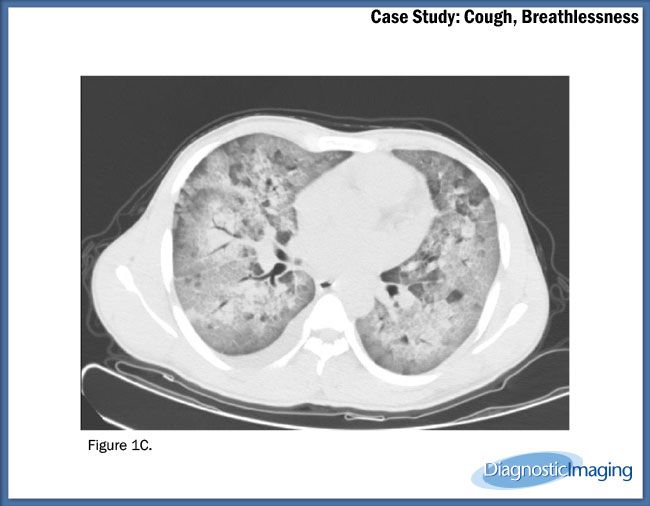

Case History: 22-year-old patient presents with cough and breathlessness.